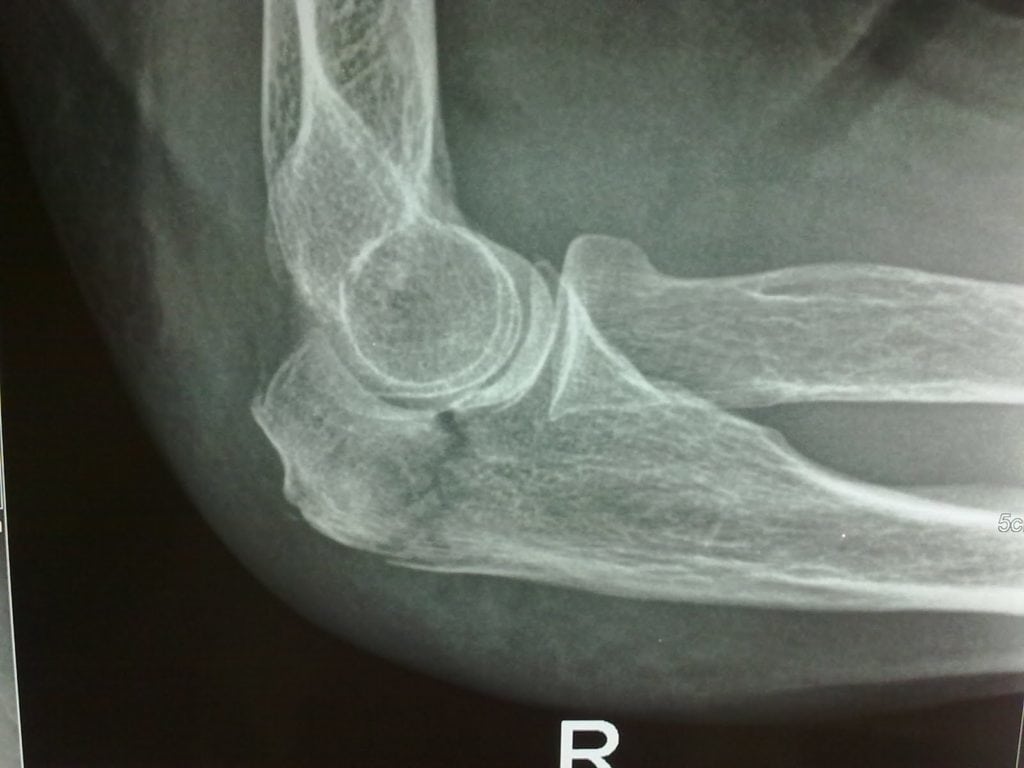

При переломах образующих его костей происходит ограничение функций всей руки. Возникают препятствия при попытке выполнить любое элементарное движение, например, развернуть кисть вверх. Полное восстановление функций локтя возможно только при размещении костей и их отломков в анатомическом положении, обеспечивая их быстрое сращение. Ведущий метод диагностики всех переломов локтевого сустава — рентгенография. Метод лечения зависит от локализации и тяжести травмы, возраста пациента. Если консервативное лечение (наложение гипса) не окажет эффекта, больного готовят к хирургической операции.

При таких травмах обычно повреждения локализованы в верхних третях локтевых костей. Происходит перелом локтевого отростка (переломо-вывихи Монтеджи).

Если произошло спровоцированное тягой трицепса смещение фрагмента, то проводится только оперативное лечение. Хирург восстанавливает хрящевые и костные ткани, а затем фиксирует отломки спицами и проволокой. Удаляют спицы примерно через полгода после оценки состояния локтя. А пластины извлекаются позже — через 1-2 года.

Благодаря близкому расположению локтевого отростка к коже операция длится недолго и не представляет сложности. Но есть и исключения — многооскольчатые переломы с повреждениями венечных отростков. Они закрепляются специальными хирургическими металлическими конструкциями.